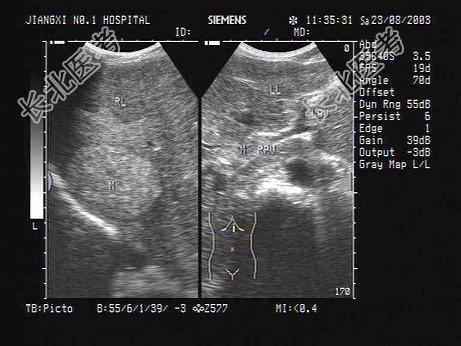

- 单项选择题某患者肝脏声像图表现,最有可能的诊断是   (   )

A、原发性肝癌并门脉癌栓

B、肝转移癌

C、肝硬化并门脉血栓形成

D、肝硬化并门脉海棉样变性

E、弥漫性肝癌